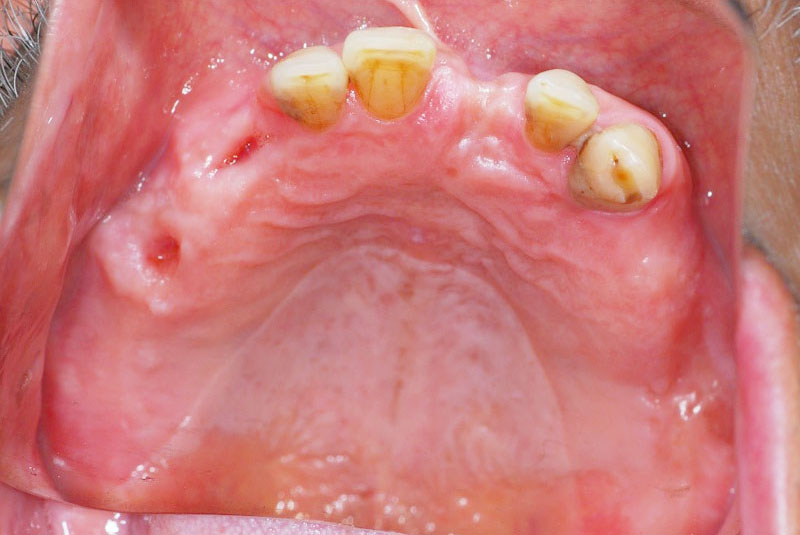

多数歯欠損のインプラント(サイナスリフト・GBR併用)

- 患者

- 50代男性

- 主訴

- インプラントができないかどうか相談。

できるだけきれいにしたい。

- 治療経過

- 前医にて上顎部分入れ歯を装着、下顎の奥歯を抜歯した状態で来院されました。また下顎の両側の臼歯の抜歯が必要と診断されたとのことでした。前医にインプラントを相談したが下顎はできるが、上顎は骨がないことを理由にインプラント不可能と診断され当院受診されました。診断の結果、下顎臼歯は保存可能、上顎臼歯部は左右上顎洞に対する骨造成(サイナスリフト)、前歯部はGBRにて骨造成を行い、インプラント埋入を行いました。

サイナスリフトはかなり専門性の高い外科処置であるため対応できる歯科医師は限られます。そのためショートインプラントや傾斜埋入で対応されることも多いですが、患者さんの年齢や希望を伺いながら当院では必要であれば積極的に行っております。その他不良補綴物の除去、根管治療、虫歯治療を行い全顎に対して審美的修復を行い治療終了までに2年を要しました。ちなみに当院では1本も抜歯は行いませんでした。保存できる歯と抜歯の必要な歯をしっかり診断することも必要です。